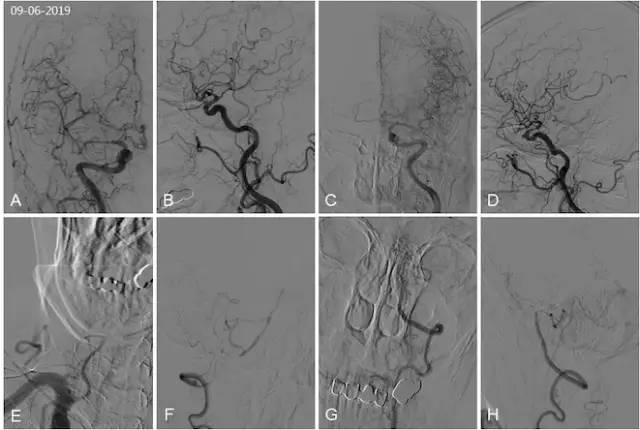

全麻下(2019-09-13)右桡动脉入路,将5F导引导管在泥鳅导丝导引下置于右椎动脉V2远端,造影显示右侧椎动脉V3-4段闭塞(图5A)。Synchro 300 cm微导丝配合Echelon-10微导管在经5F导引导管送入,路径图下微导丝配合微导管顺利到达闭塞段中段(图5B),微导丝到达闭塞远端有阻力,继续前行见微导丝走形在远端正常血管边缘,考虑微导丝进入夹层(图5C)。撤出微导丝再次尝试也未获成功,此刻造影显示右椎动脉V3段以远闭塞,术前向右小脑后下动脉代偿供血的右椎动脉分支消失(图5D)。完全撤出微导管及微导丝,造影显示闭塞段部分再通,内有充盈缺损,远端V4段及右小脑后下动脉有顺行显影(图5E)。观察10分钟后重复造影显示右椎动脉V3段以远完全闭塞(图5F)。行右股动脉穿刺,将5F导引导管在泥鳅导丝导引下置于左椎动脉开口行造影检查示:左椎动脉V4段发出左小脑后下动脉以远闭塞。脊髓前动脉向基底动脉及右椎动脉末端及右小脑后下动脉代偿(图5G,H)。考虑继续开通治疗风险高,遂结束手术。

图5

术后立即复查头CT未见出血(图6A,B)。

术后颅内动脉CTA:双椎动脉V4段闭塞;与术前CTA相比,右椎动脉V3闭塞段长度有增加(图6C,D)。

图6